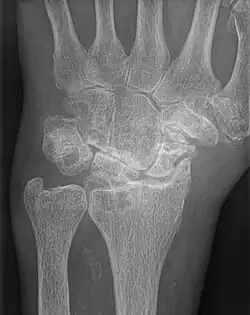

AP wrist x-ray demonstrating Stage III scapholunate advanced collapse

Stage III SLAC wrist

Stage III SLAC wrist involves the entire radioscaphoid joint and the capitolunate joint.[3] The PA wrist x-ray will demonstrate sclerosis and joint space narrowing between the lunate and capitate. Over time, the capitate will migrate proximally into the space created by the scapholunate dissociation.[2] The radiographic findings in Stage III SLAC wrist are synonymous with the Terry-Thomas sign, indicating complete scapholunate dissociation.[2]